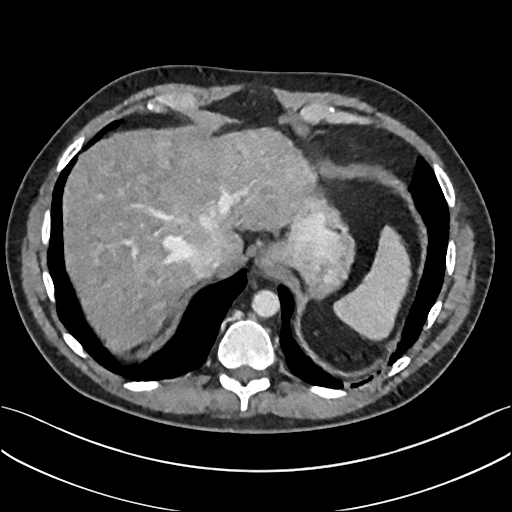

To demonstrate the effectiveness of the proposed network, we perform the qualitative comparisons over three representative abdominal images presented in Figs. 3, 5 and 7. For better evaluations of the image quality with different denoising models, zoomed regions-of-interest (ROIs) are marked by red rectangles and shown in Figs. 4, 6 and 8 respectively. Note that all results from different denoising models focus on two aspects: content restoration and noise-reduction. All CT images in axial view are displayed in the angiography window [-160, 240]HU.

The real NDCT images and corresponding LDCT images are presented in Figs. 3a and 3b. As observed, there are distinctions between ground truth (NDCT) images and LDCT images. Figs. 3a and 7a show the lesions/metastasis. Fig. 5a presents focal fatty sparing/focal fat. In Figs. 4a, 6a and 8a, these lesions can be clearly observed in NDCT images; in contrast, from Figs. 4b, 6b, and 8b, it can be seen that the original LDCT image is noisy, and lacks structural features for task-based clinical diagnosis. All adopted denoising models suppress noise to some extent.

From Figs. 7 and 8, we can see mean-based and SL-based methods work well with effective noise suppression and artifact removal. However, the illustrations in Fig. 8 show that these methods blur the local strutural features. Our proposed SMGAN-based methods present a better edge preservation than the competing methods.

In Figs. 7 and 8, it can be found that the SMGAN-based methods can achieve better anatomical feature preservations and visual quality than other state-of-the-art methods.

Figs. 7 and 8 demonstrate that the SMGAN-3D can be used to provide improved anatomical feature preservation over other state-of-the-art methods.